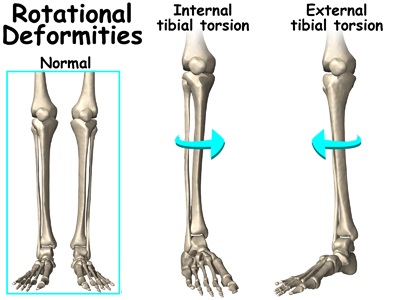

الف) تورشن تیبیا یا چرخش ساق به داخل

علت تورشن تیبیا Tibial torsion چرخیده بودن استخوان تیبیا یا درشت نی به داخل در زمان جنینی بچه است. چون استخوان درشت نی به سمت داخل چرخیده است مچ و کف پا هم که به آن متصل هستند به سمت داخل کج میشوند و در نتیجه بچه کف پایش را به سمت داخل میگذارد .

چرخش استخوان تیبیا به داخل در همه بچه ها تا سن دو سالگی تا حدودی وجود دارد که با بالا رفتن سن این چرخش کاهش میابد و منظور از این بیماری وقتی است که این چرخش بیش از حد طبیعی شود .

این بیماری در اکثر بچه ها تا سن دو سالگی و در اکثر قریب به اتفاق آنها تا قبل از سن مدرسه بطور خودبخود خوب میشود. اسپلینت، کفش های مخصوص و ورزش و نرمش هیچ تاثیری بر روی این تغییر شکل مادرزادی ندارد .

اگر چرخش استخوان درشت نی بچه تا بعد از 10 سالگی به اندازه کافی اصلاح نشود و بچه به خاطر این چرخش زیاد مشکل فراوانی در راه رفتن داشته باشد نیاز به تصحیح چرخش با استفاده از عمل جراحی دارد. این عمل جراحی معمولا موقعی انجام میشود که مقدار چرخش باقیمانده در استخوان تیبیا بیش از 35 درجه باشد

جراحی با انجام استئوتومی است بدین معنا که پزشک جراح استخوان تیبیا را در بالای مچ پا شکانده و پس از تصحیح چرخش قطعات استخوانی را در وضعیت مناسب به توسط پیچ و پلاک به هم فیکس کرده تا جوش بخورند .